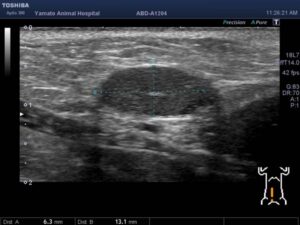

ワンちゃんが乳腺にできた複数のシコリを気にされて来院されました。bilateral mastectomyで対応しました。摘出後の病理組織検査の結果は、「R3-4間腫瘤:乳腺癌(複合型)」でそれ以外は「良性乳腺混合腫瘍」でした。無事元気に退院し、その後再発もなく経過は良好です。よかったね。